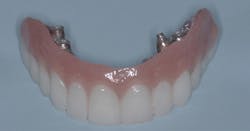

The most well-known implant-supported fixed restoration concept for edentulous patients was taught by Per-Ingvar Brånemark, MD, PhD, more than 30 years ago. Typically, six implants were placed on each arch, located anterior to the sinus on the maxillary and anterior to the mental foramen on the mandibular. When the implants had integrated into the bone over several months, a prosthesis was screwed onto the implants. Cantilevers were extended on each side of the arch, about one centimeter distal to the implant-supported portion of the prosthesis. The prostheses usually included 12 teeth, including the first molar only distally. Overall, these prostheses served well (figure 1). If one or two implants failed, which occasionally happened, the prostheses usually were still viable and functioned adequately.

Figure 1: Patient with maxilla restored with the previous popular concept using six implants as described in the narrative